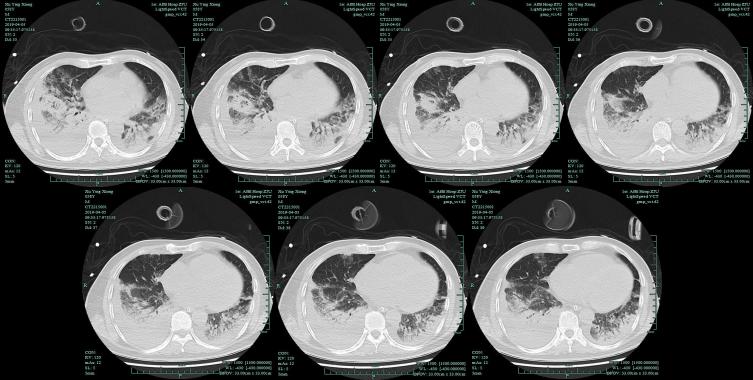

肺部CT(治疗后)提示双肺弥漫性病变,小叶性肺炎,左下肺斑片状阴影。

由于病人入院时病情严重,担心进行肺泡灌洗对他会有影响,所以进行了血mNGS检测……